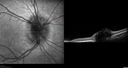

8 year old boy with headache and nausea. He had a negative MRI. Images show hyper FAF from drusen and no leakage on FA. No spinal tap was done. VA was 20/40 both eyes.

Disc drusen 8 year old boy - fluorescein shows no leakage204 views8 year old boy with headache and nausea. He had a negative MRI. Images show hyper FAF from drusen and no leakage on FA. No spinal tap was done. VA was 20/40 both eyes.00000